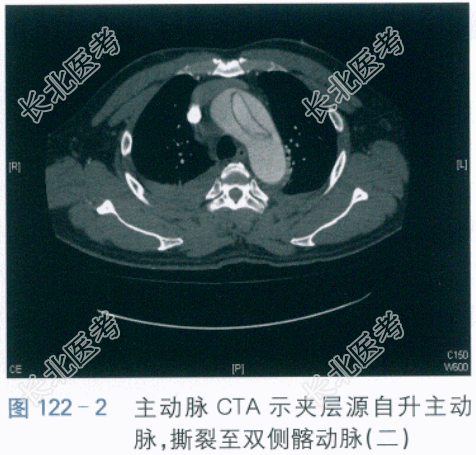

实验室和影像学检查:血常规:WBC 12.6×10⁹/L,N79%,PLT 102×10⁹/L。肝功能:TB/DB14.6/5.2(μmol/L),A/G32/36(g/L),ALT/AST 54/45(IU/L)。肾功能:Cr76μmol/L,BUN5.2mmol/L。凝血功能:D-二聚体7.28mg/L,INR1.35,APTT32s,PT13s。心肌酶谱:cTnT0.05ng/ml,CK123IU/L,CK-MB24IU/L,NT-proBNP2134pg/ml。心电图检查:窦性心律,急性下壁、后壁心肌梗死不能除外。两侧胸腔积液伴两下肺膨胀不全,心包少量积液。如图122-1、图122-2、图122-3所示。